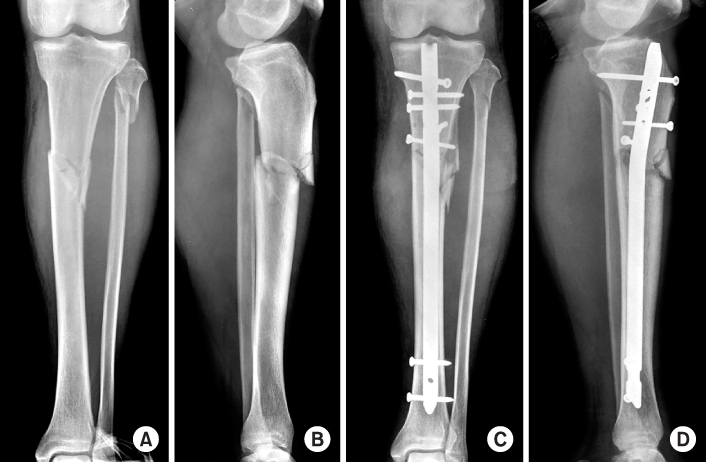

Fig. 8

(A, B) Initial radiographs show the proximal tibial fracture at the proximal meta-diaphyseal junction.

(C, D) Postoperative radiographs show good alignment of the fracture fixed with a locked tibial nail and blocking screws to prevent malalignment. A blocking screw was placed lateral to the central axis to prevent valgus angulation and the other blocking screw was placed posterior to the central axis to prevent apex anterior angulation.

Fig. 8 (A, B) Initial radiographs show the proximal tibial fracture at the proximal meta-diaphyseal junction. (C, D) Postoperative radiographs show good alignment of the fracture fixed with a locked tibial nail and blocking screws to prevent malalignment. A blocking screw was placed lateral to the central axis to prevent valgus angulation and the other blocking screw was placed posterior to the central axis to prevent apex anterior angulation.